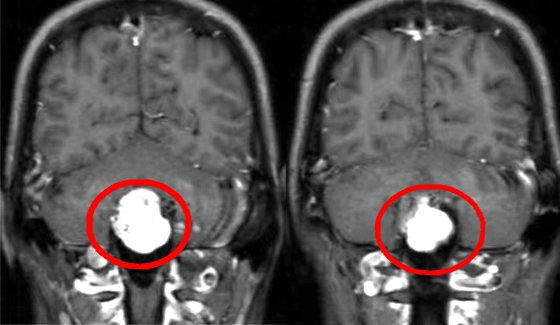

近日,湘雅常德医院神经外科在袁贤瑞教授和张梨副主任医师的带领下成功开展了一例桥小脑角区巨大脑膜瘤切除术。 近年来,朱阿姨的耳边持续性出现“嗡……嗡……...